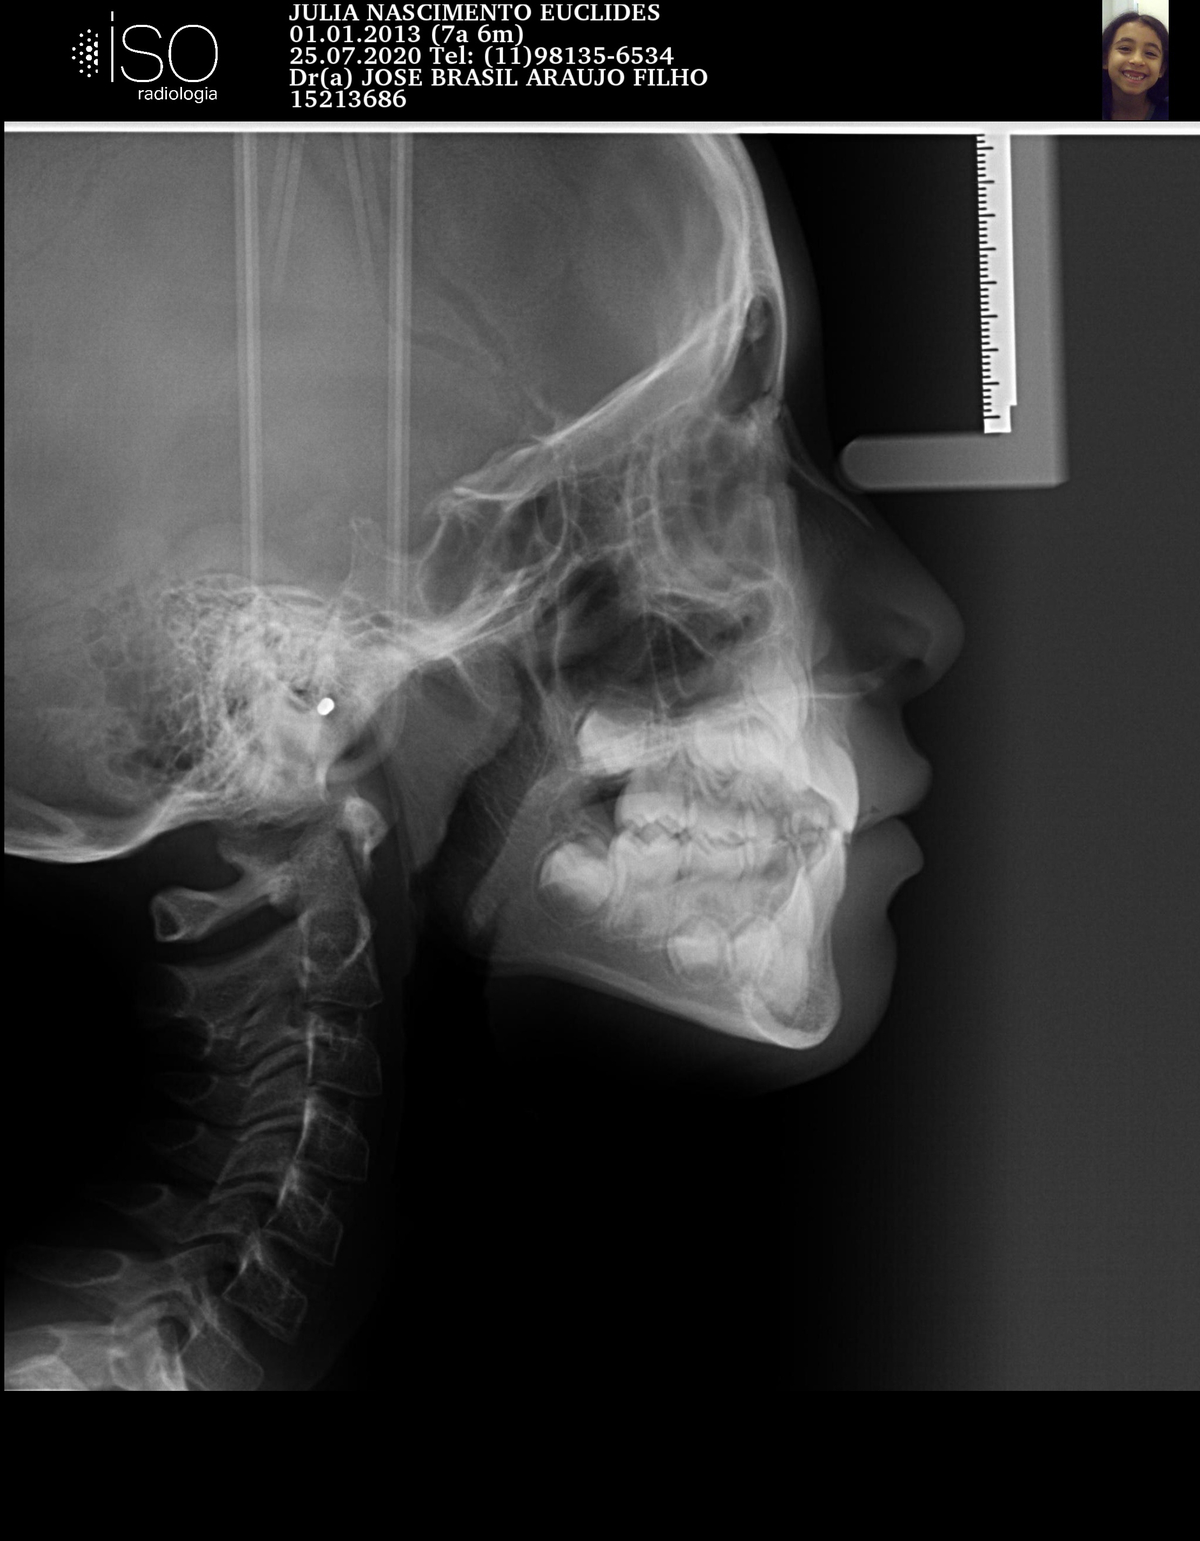

ORTODONTIA MIOFUNCIONAL

J.N.E.